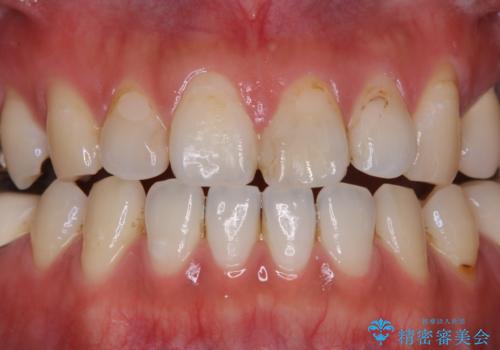

- 虫歯治療を始める前に、まずはしっかり汚れを取りたいとのことで来院されました。歯石やステインが分厚く付着していたため、PMTC60分コースを行いました。

歯の表面に、茶色く色が残っている所がありますが、これは詰め物の変色によるものです。以前に、CR(コンポジットレジン)による虫歯治療がされています。

CRは経年的劣化や、着色してしまうことがあります。PMTCでクリーニングを行うと、古いCRが目立つことがあるため、気になる際は詰め替えを行います。

茶色くなっている部分が、着色なのか、劣化なのか、虫歯によるものなのかは判別が難しいことがあります。そのため、定期的にPMTCを行うことで状態の確認が的確に行えます。